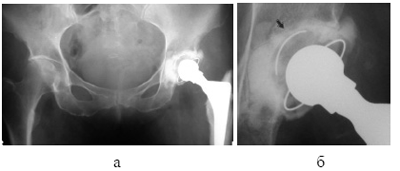

Рис. 6. Использование позиционирующих винтов (случай 2): а. тотальное цементное эндопротезирование правого ТБС, б. тот же снимок в увеличении — позиционирующие винты по периметру впадины.

впадины коротких кортикальных винтов (рис. 4). После обработки римированием внутрисуставного хряща, производится пробная установка кубка во впадине, при этом намечаются места установки позиционирующих винтов. После их установки кубок опять «вхолостую» устанавливается во впадине и кручением винтов (завинчивание или развинчивание) кубок позиционируется в оптимальную для имплантации позицию. Далее следует заливка цемента и стандартное закрепление ацетабулярного кубка, позиционирующие винты исключают возможность ошибки и децентрации.

Тем самым решается ряд важных проблем во время цементировки ацетабулярного кубка эндопротеза. Во-первых, оставшиеся вне кости головки винтов обеспечивают равномерное пространство для цементной мантии. Во-вторых, их высота, достигаемая завинчиванием или развинчиванием, по разному упираясь в кубок, позиционирует его, чем исключается возможность децентрации или изменения угла во время цементировки. И наконец, имплантированные винты создают дополнительную фиксацию и, наряду с отверстиями в дне вертлужной впадины, увеличивают контактную поверхность с цементом (рис. 5и6).